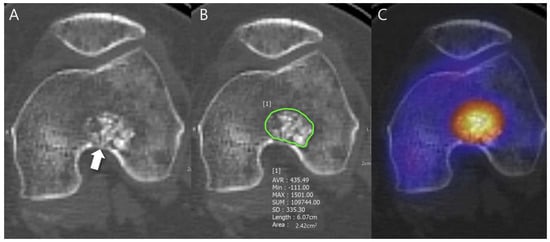

Any aggressive CT features for the grading of central cartilaginous bone tumors including (i) deep endosteal scalloping ≥ 2/3 of the normal cortical thickness (Figure 1), (ii) extensive endosteal scalloping ≥ 2/3 of the lesion length (Figure 2), (iii) expansile cortical remodeling (Figure 3), and (iv) cortical destruction with or without soft tissue extension (Figure 4) were also evaluated. The CT images were evaluated in conjunction with the plain radiographs and/or MRI. After finishing the independent review, a consensus review of the CT was performed. The two radiologists reviewed the CT images together to reach a final consensus on discrepant interpretations from the independent reading.

Figure 3. Expansile cortical remodeling in a patient with CS2 in the proximal femur. (A) An axial CT image shows a lobulated mass containing chondroid matrix mineralization and expansile cortical remodeling (arrows). (B) A plain radiograph shows a lobulated mass with expansile cortical remodeling (arrows) with cortical thickening (arrowhead).